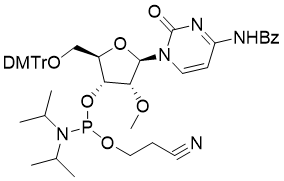

馬鞍山致研生物醫(yī)藥科技有限公司成立于馬鞍山市鄭浦港新區(qū)現(xiàn)代產(chǎn)業(yè)園。公司專(zhuān)注于生物小分子、醫(yī)藥中間體相關(guān)產(chǎn)品的研發(fā)和生產(chǎn),產(chǎn)品主要包括DNA亞磷酰胺單體、RNA亞磷酰胺單體、特殊單體以及按照客戶(hù)要求定制的RNA和DNA,并且公司提供定制合成等方面的研究服...

馬鞍山致研生物醫(yī)藥科技有限公司成立于馬鞍山市鄭浦港新區(qū)現(xiàn)代產(chǎn)業(yè)園。公司專(zhuān)注于生物小分子、醫(yī)藥中間體相關(guān)產(chǎn)品的研發(fā)和生產(chǎn),產(chǎn)品主要包括DNA亞磷酰胺單體、RNA亞磷酰胺單體、特殊單體以及按照客戶(hù)要求定制的RNA和DNA,并且公司提供定制合成等方面的研究服...